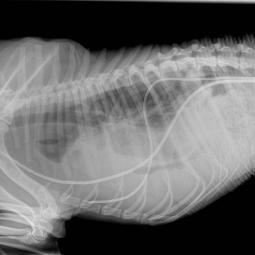

Les chirurgies thoraciques:

Ces interventions sont plus delicates que les chirurgies abdominales, une assistance respiratoire est obligatoire. Les principales interventions sont: les lobectomies pulmonaires, les pericardectomies, la ligature du canal arteriel persistant, l'exerese de masses mediastinales ...